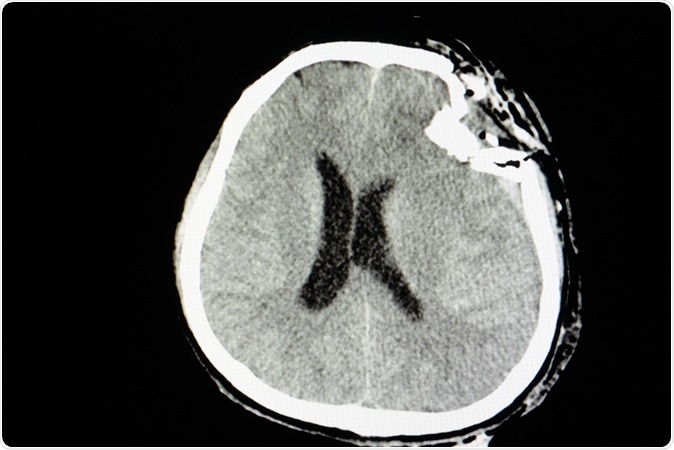

CT skull film of a patient with traumatic brain injury showing compression depression fractures of left temporoparietal bone. Image Credit: Sopone / Shutterstock